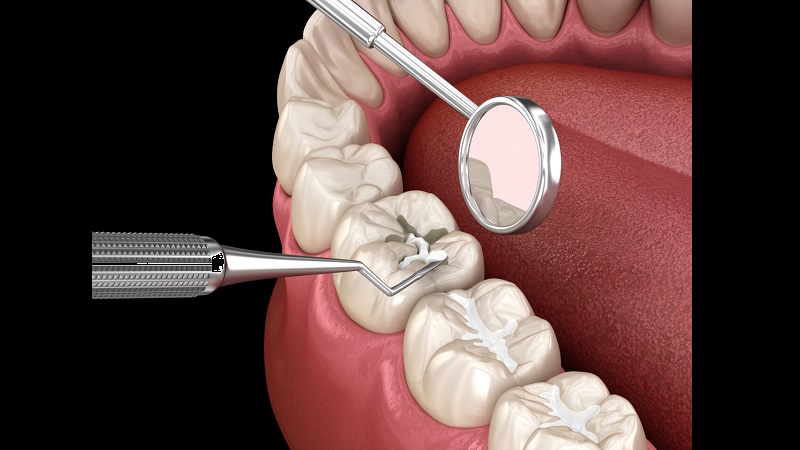

کامپوزیت (پرکننده سفید)

کامپوزیتها موادی همرنگ دندان هستند که برای ترمیم دندانهای قدامی یا حتی آسیابها استفاده میشوند. این مواد زیبایی بیشتری نسبت به آمالگام دارند و بهویژه برای دندانهایی که در معرض دید هستند، انتخاب مناسبیاند. کامپوزیت با نور مخصوص سفت میشود و به ساختار دندان میچسبد، بنابراین نیاز به تراش کمتری دارد. البته این ماده در مقایسه با آمالگام هزینه بیشتری دارد و برای نصب آن زمان بیشتری لازم است. همچنین در صورت وارد شدن فشار بیش از حد، ممکن است زودتر از سایر مواد دچار شکست شود.